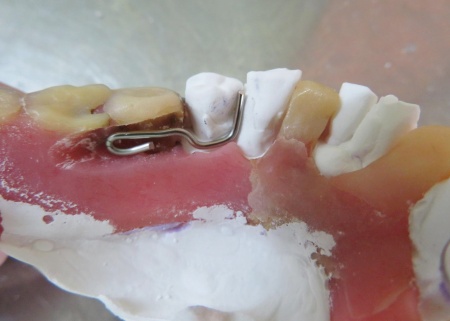

治療前

治療中

クラスプを固定する場所を削りました